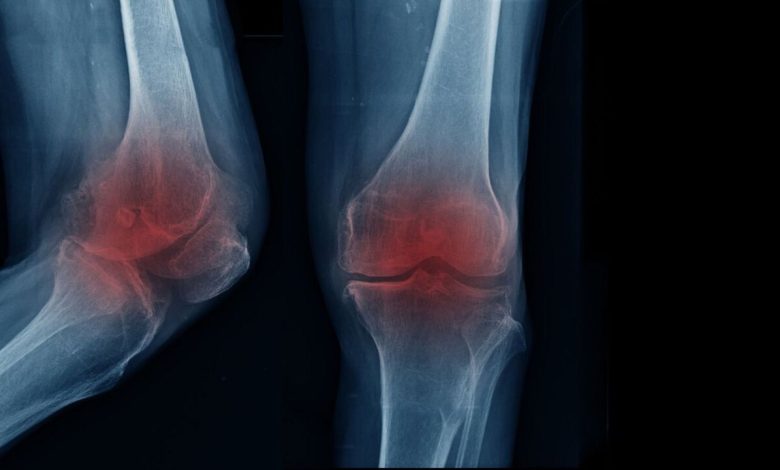

متخصص ارتوپدی و فلوشیپ جراحی زانو با بیان اینکه مفصل زانو یکی از فعالترین بخشهای بدن به شمار میرود و در طول زندگی فشار زیادی را تحمل میکند، تصریح کرد: با گذشت زمان و افزایش سن، لایه غضروفی این مفصل به تدریج نازک و فرسوده میشود و همین روند میتواند زمینهساز بروز آرتروز یا ساییدگی زانو باشد.

اکبری اقدم با بیان اینکه زمانی که این غضروف کارکرد طبیعی خود را از دست بدهد، حرکت مفصل با مشکل همراه و درد و محدودیت حرکتی ظاهر میشود، ادامه داد: بروز آرتروز زانو همیشه به یک عامل مشخص محدود نمیشود و دلایل گوناگونی در ایجاد آن نقش دارند.

متخصص ارتوپدی و فلوشیپ جراحی زانو با تاکید بر اینکه شایعترین علامت آرتروز زانو درد است که به طور معمول در مراحل ابتدایی هنگام راه رفتن یا فعالیت بروز میکند، اضافه کرد: با پیشرفت تخریب غضروف، شدت درد افزایش مییابد و ممکن است حتی در حالت نشسته یا استراحت نیز فرد را آزار دهد.

اکبری اقدم با بیان اینکه علاوه بر درد، احساس خشکی مفصل به ویژه پس از بیدار شدن از خواب، کاهش دامنه حرکتی و دشواری در انجام حرکات روزمره نیز از نشانههای رایج این بیماری محسوب میشود، افزود: اگرچه افزایش سن نقش مهمی در ابتلاء به آرتروز زانو دارد، اما سبک زندگی نیز تأثیر قابل توجهی در زمان بروز آن ایفا میکند.